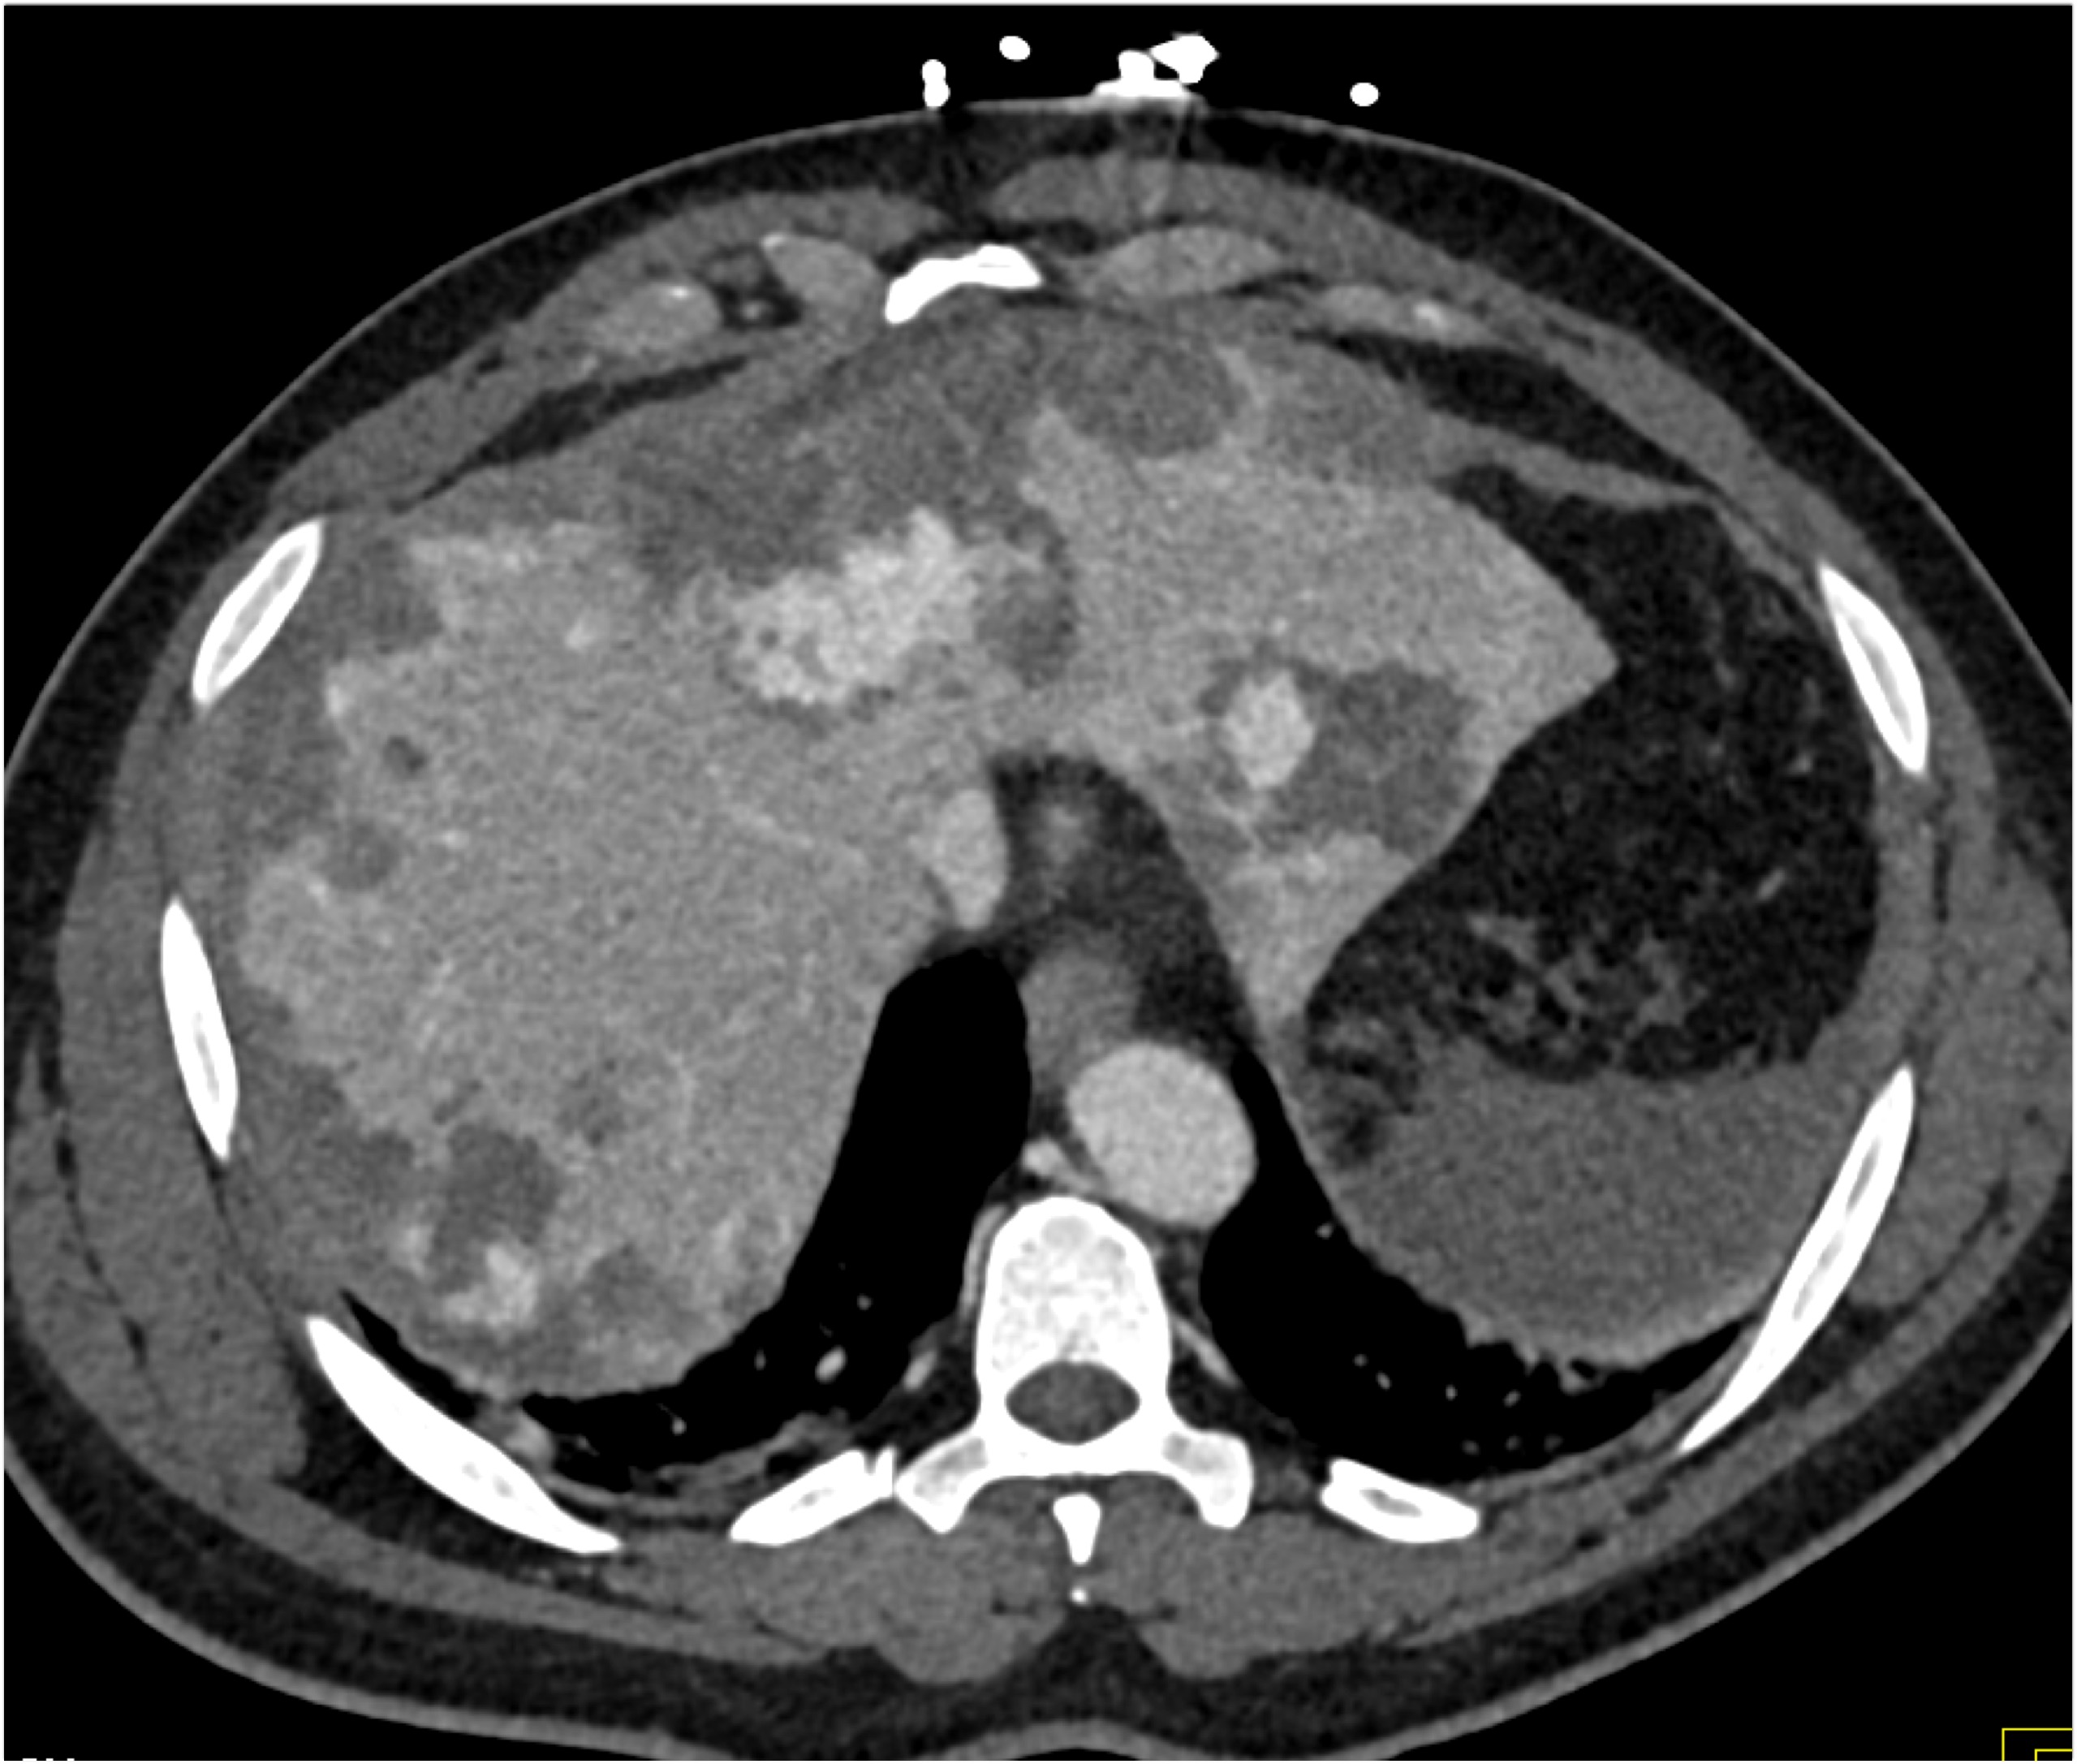

8) The most likely diagnosis in this case is?

clear cell renal cell carcinoma

large B-cell lymphoma

seminoma

renal abscess